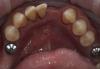

Art 7 Опубликовано 30 марта, 2013 Поделиться Опубликовано 30 марта, 2013 фото до фото после модельпациент хочет закрыть дефект при помощи имплантации,но чуть позжени чего временного не хотел,кое как уговорил на эту конструкцию чтобы сохранить место 1 Ссылка на комментарий

Art 7 Опубликовано 30 марта, 2013 Автор Поделиться Опубликовано 30 марта, 2013 А как было до?Небольшая скученность, фото нет. Зубы 41.42 я предполагаю пойдут на удаление к тому времени как пациент созреет на имплантацию. И уже дал заочное согласие. Ссылка на комментарий

Bobby Опубликовано 30 марта, 2013 Поделиться Опубликовано 30 марта, 2013 Поделитесь мыслями Вместо 4-х нижних резцов ставится 2 имплантата и делается мостовидная конструкция из 4-х единиц. 2 Ссылка на комментарий